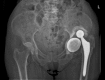

Case report: Painless chronic liner dissociation of a total hip arthroplasty

Background: Dislocation or liner dissociation of a total hip prosthesis usually results in pain and discomfort. Although several reports describe chronic dislocation and its treatment, chronic liner dissociation is an unreported complication.

Case description: We report an unrecognized dissociation and displacement of the liner of a total hip prosthesis after revision THA. The patient had virtually no pain or functional restrictions. The patient's only complaint was pain on the contralateral side, associated with a leg-length discrepancy. Since the patient had no complaints relative to the liner dissociation we elected not to pursue further treatment. The contralateral pain was treated successfully with a shoe lift.